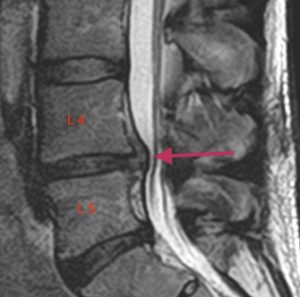

Lannerangan magneettikuva 2

Sivuprofiili, jossa näkyy nikamarakenteita tarkemmin.